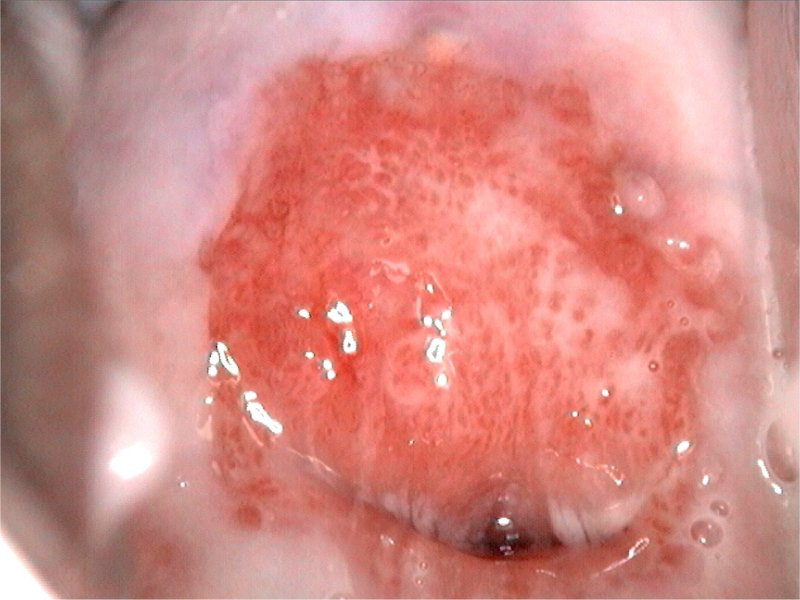

No exame ginecológico, teremos dois achados característicos importantes para o diagnóstico diferencial: o colo uterino terá aspecto de morango/framboesa e o Teste de Schiller (iodo) será tigroide. O Teste das Aminas pode ser positivo ou negativo. O exame da lâmina a fresco mostrará as tricomonas móveis e o pH será > 5.